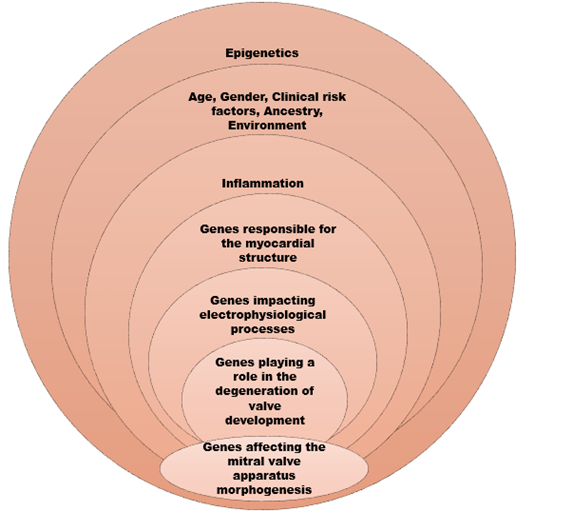

A recent metanalysis, extracted three cardiomyopathy related genes, namely ALPK3, BAG3, and RBM20 implying the potential interdependence between MVP and cardiomyopathies.(28) This was the largest metanalysis of GWAS to date located in total 16 genetic loci, responsible for the AMVP phenotype, by combining the knowledge from contemporary genotyping algorithms with transcriptional and proteomic analysis from mitral valve tissue.

Taking this further, Roselli et al, created a polygenic risk score for prediction of MVP risk, involving the age, gender, clinical risk factors (ie hypertension, diabetes, heart failure, myocardial infarct) and ancestry components, which is a promising attempt for future screening, management and potential therapeutic targets.

Moreover, the role of environmental factors and epigenetics in arrhythmic mitral valve phenotype are yet to be determined. Regulatory roles of RNA-binding proteins on splicing and variants in deep intronic sequences point towards enlightening directions in the era of rapidly evolving genomic technology.(29,30)

Taking into consideration the aforementioned data in our armamentarium, the image below depicts and summarises the genes and processes participating in AMVP genesis. (Figure 3)